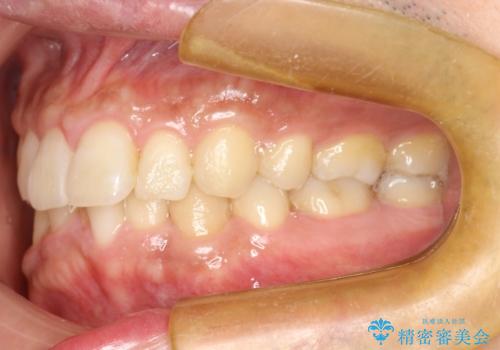

- 以前、上下左右4本抜いてワイヤー矯正をしていた方で、後戻りで下の前歯のガタガタを気にして来院されました。

マウスピース矯正にて、下の歯はIPR(歯と歯の間を削る)を入れることでガタガタの改善、咬み合わせの深さも改善をはかる治療計画をたてました。

歯と歯の間を削って隙間を作って矯正をしています。